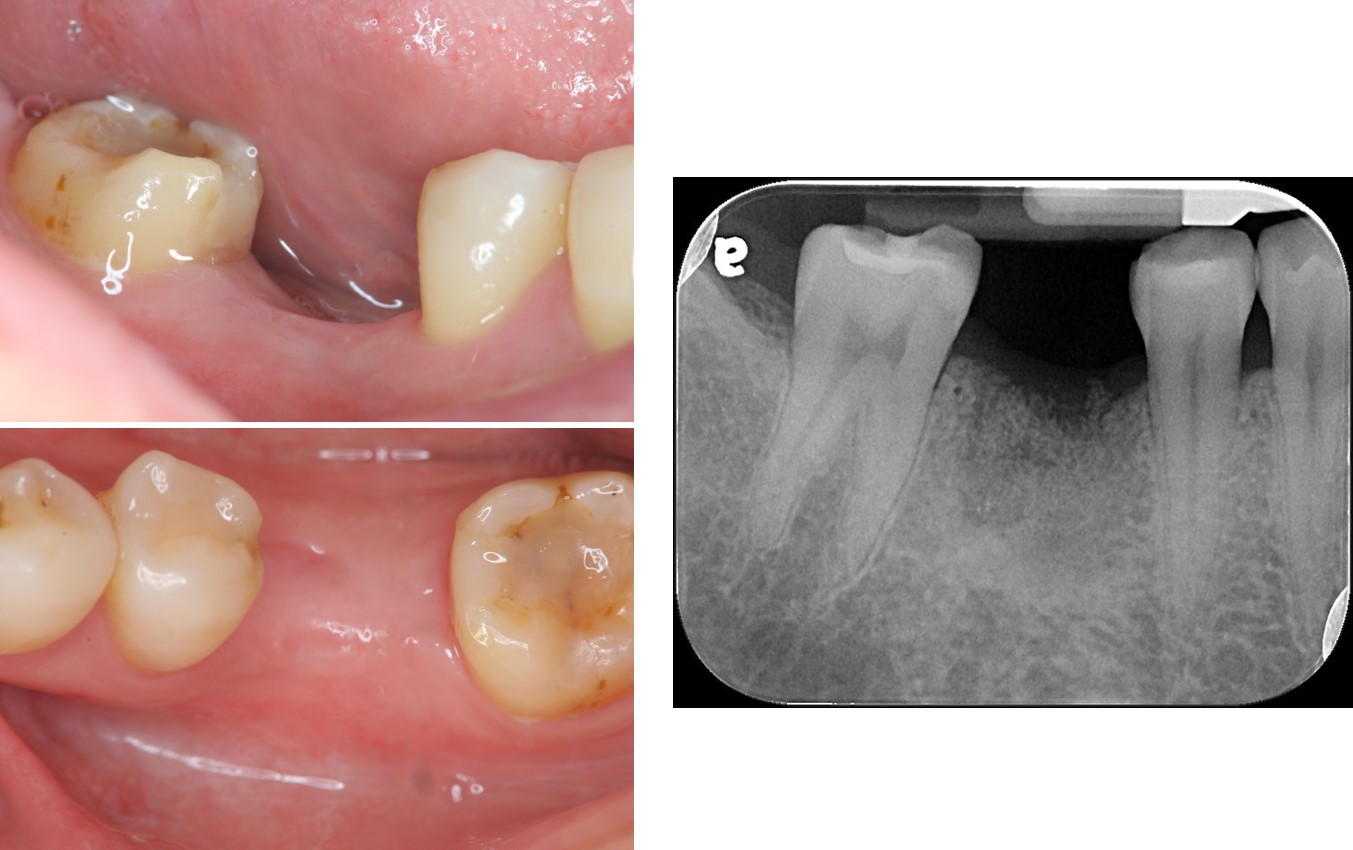

本病患嗛為多前有製作過瓷牙、釘柱等治療,但因長期咬硬的食物,導致牙齒斷裂,長胞,經診斷無法保留牙齒,溝通後,患者決定植牙

治療前,牙齒長膿胞

治療前,牙骨已破壞